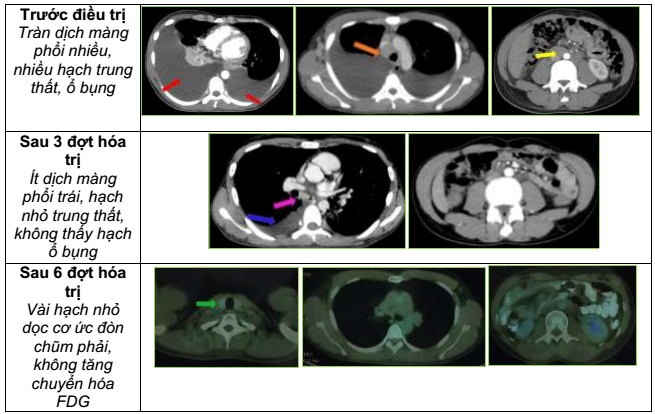

Tóm tắt các triệu chứng lâm sàng, cận lâm sàng:

u51

Hình ảnh trước và sau điều trị